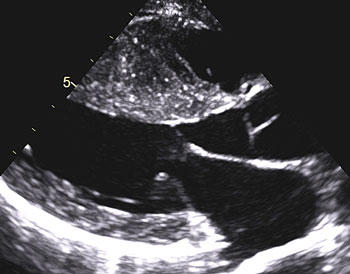

Bilddiagnostik med bland annat ultraljud och doppler

Ultraljudsundersökning av hjärtat påvisar ­hypertrofi – oftast i kammarseptum, men alla delar av hjärtat kan påverkas (Figur 3, 4 och 5). Det förekommer en variant med enbart apikal hypertrofi. Med dopplerundersökning kan förhöjda hastigheter över vänsterkammarens utflödesregion påvisas i vila hos ungefär en tredjedel, medan hos ytterligare cirka en tredjedel förhöjd gradient (tryckskillnad) kan provoceras fram genom fysiologisk belastning, Valsalvas manöver eller läkemedel. Den metod som numera rekommenderas är fysiologisk belastning på cykelergometer eller gångmatta, vilket är av värde om ingen gradient ses vid vila då anamnesen indikerar en dynamisk gradient.

Inte sällan ses läckage i mitralisklaffen och en framåtgående rörelse av vanligtvis det främre klaffseglet under systole. Vänster förmak kan vara förstorat sekundärt till höga fyllnadstryck.

Figur 5. Ekokardiografi med doppler visar »dolkformad« kurva av utflödet från vänster kammare.